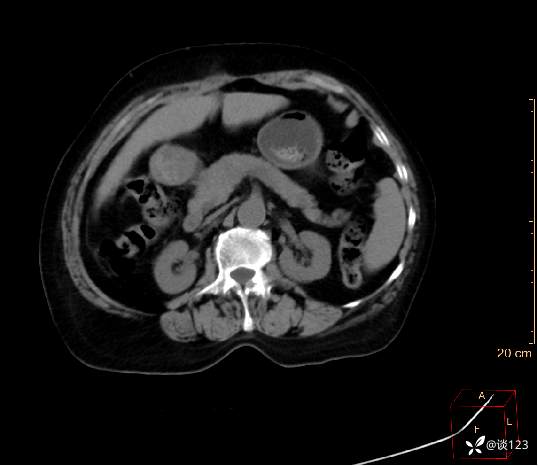

急诊影像检查: 头颅CT平扫+全腹部CT平扫 1、双肾囊性灶;2、双侧放射冠区多发腔隙性脑梗塞;3、脑萎缩。

先做的CT:

C-

A

V

D